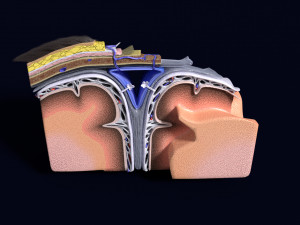

A blend model of brain along with its covering layers (meninges), skull bone and scalp labelled in detail and anatomically precise. The parts depicted are white, gray, pia, arachnoid, dura, bone, skin, fat, aponeurosis, periosteum, falx cerebri and more.

The material is high resolution image textures and normal maps based on non overlapping UVs. The texture and normal maps are packed with the blend file itself.